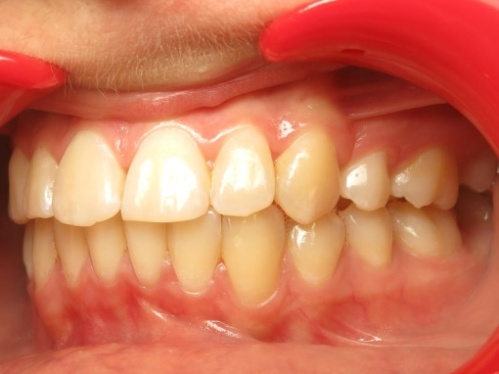

4 - Esthétique du sourire et profil préservé

Le traitement a permis à la patiente de retrouver un sourire harmonieux. Les lèvres n’ont subi aucun recul et l’angle nasolabial est resté inchangé, préservant l’équilibre naturel du profil. Ce résultat esthétique et fonctionnel montre que, dans certains cas, les extractions peuvent représenter la meilleure option thérapeutique pour traiter un encombrement et une classe II tout en conservant l’harmonie du visage. Dans ce cas précis, la conservation de toutes les dents était inenvisageable.